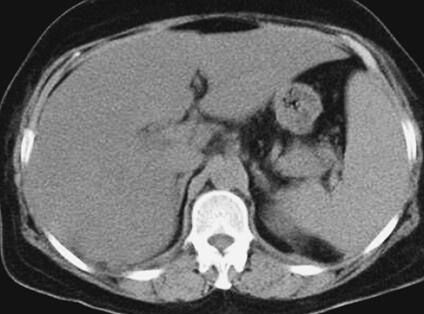

患者,女性,59岁。因“发热8天,上腹部隐痛、腹泻伴胸闷7天”于2011年7月8日入院。患者8天前出现发热,39.5℃,无畏寒、寒战,在当地卫生院予输液治疗(具体不详),症状未好转。7天前出现上腹部隐痛、腹泻,日约4~5次,黄色稀便,伴胸闷,遂就诊于当地镇医院,心电图检查正常,拟“中暑”,予针灸等治疗后无好转。2天前就诊于当地县人民医院,查血常规:WBC 8.4×109/L,N 89.2%,Hb 102g/L,PLT 92×109/L;肥达反应阴性;肝功能:ALT 104IU/L,AST 144IU/L,TP 55g/L,ALB 27g/L;腹部CT:脂肪肝,脾肿大;胸部CT:两肺少许炎症,左侧可疑少许胸腔积液,拟败血症,中毒性肝炎,伤寒住院治疗;期间体温波动于38~39℃,血压波动于80/50~90/60mmHg,予多巴胺[6.0μg/(kg·min)]升压,予亚胺培南-西司他汀钠联合头孢曲松抗感染治疗,病情无好转,仍有发热、腹泻、上腹部隐痛不适,并出现尿量减少、血肌酐升高。于7月8日转笔者医院急诊,测血压[多巴胺6.0μg/(kg·min)维持]89/55mmHg,血常规:WBC 10.28×109/L,N 89.4%;Lac 2.3mmol/L,CRP>90.0mg/L,Cr 141μmol/L,cTnI 6.02μg/L,BNP 577pg/ml;胸腹部CT:两下肺背侧散在炎症,两侧胸腔少量积液,慢肝样病变,胆囊结石(图1、图2);腹部B超:脂肪肝,脾偏大,拟发热待查,心肌炎?感染性休克?,予补液、亚胺培南-西司他汀钠控制感染,多巴胺升血压,为进一步治疗拟上述诊断收入急诊重症监护病房。既往史:40年前发现胆囊结石。

图2 胸腹部CT:脾肿大(7月8日)